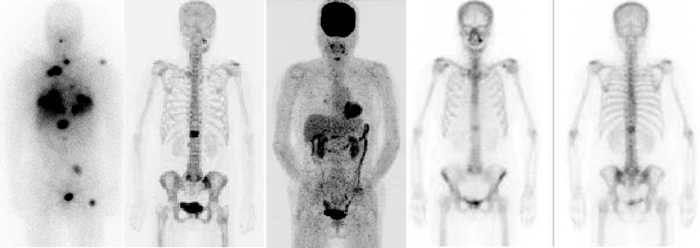

Multiple bone metastases of DTC.

From left to right: 131I scintigraphy, 18F-fluoride PET/CT, 18F-FDG PET/CT, anterior and posterior planar bone scintigraphy. Bone metastases at left pelvis and thoracic spine could be detected by all the 4 modalities.